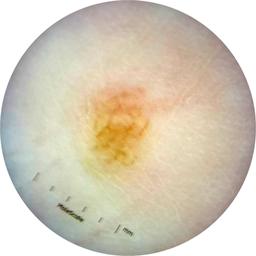

ISIC_1376863

IP_6274125

IL_8319447

Clinical

Field Value

acquisition_day 229

age_approx 40

anatom_site_general oral/genital

anatom_site_special oral or genital

concomitant_biopsy False

diagnosis_1 Benign

diagnosis_confirm_type single image expert consensus

family_hx_mm True

image_manipulation instrument only

image_type dermoscopic

lesion_id IL_8319447

patient_id IP_6274125

personal_hx_mm True

sex female